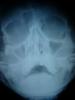

Большой Зеленый Опубликовано 17 декабря, 2009 Поделиться Опубликовано 17 декабря, 2009 А вы не тот доктор который это делал? Ваще то при таких делах в приличных местах делают КТРот не открываться может и из за смещения скул.кости, что чаще и бываетПока не поздно - сделайте КТ в другом медучреждении и если венечный отросток контактирует со скуловой - реоперацияЕще надо смотреть дно глазницы - если его уже нет - надо предпринимать меры чтобы не было гипоэнофтальма (западения глаза)А в остальном все будет хорошо Я не тот доктор . Но таких вещей делал очень много .Даже по этому плохому снимку видно что смещение не большое. И вообще чтобы скуловая кость заклинила венечный отросток Мне такого не встречалось.. Ссылка на комментарий

oleg Vl Опубликовано 18 декабря, 2009 Поделиться Опубликовано 18 декабря, 2009 (изменено) Я не тот доктор . Но таких вещей делал очень много .Даже по этому плохому снимку видно что смещение не большое. И вообще чтобы скуловая кость заклинила венечный отросток Мне такого не встречалось..блокирует открывание скуловая дуга, но на этом снимке ее не видно, (перелом в месте перехода кости в дугу ), вообще снимок не айс. да и перелом похоже не простой т.к перелом по наружному краю орбиты не в типичном месте, не по шву. метод лечения (репозиция тампонадой), вряд ли даст хороший результат, уже давно скобами все это фиксируют или минипластинами, тогда репонировать можно очень хорошо, а под тампоном все равно проседает кость.а уж реоперация это вообще ж...аКогда работал в стационаре скуловая, была самая не любимая операция (вообще травму не любил всегда) А вы не тот доктор который это делал? Ваще то при таких делах в приличных местах делают КТРот не открываться может и из за смещения скул.кости, что чаще и бываетПока не поздно - сделайте КТ в другом медучреждении и если венечный отросток контактирует со скуловой - реоперацияЕще надо смотреть дно глазницы - если его уже нет - надо предпринимать меры чтобы не было гипоэнофтальма (западения глаза)А в остальном все будет хорошо да похоже подглазничный край цел ( по крайней мере по снимку, ну, или нет смещения). поэтому дно орбиты скорее всего тоже, хотя кт конечно не помешает, особенно если есть проблемы со зрением. скорее всего дугу не поставили как положено. Изменено 18 декабря, 2009 пользователем oleg Vl Ссылка на комментарий

CbIHAMATb Опубликовано 9 октября, 2010 Поделиться Опубликовано 9 октября, 2010 Судя по снимку-все же перлом дуги имееется(чуток срезана правая скуловая дуга).Скорее причина контрактуры именно в переломе дуги,который не репонировали.В огтношении крючка и тампона в пазухе согласе-21век на дворе))))Пытаюсь с этим бороться и ищу альтернативы у нас в отделении. Ссылка на комментарий